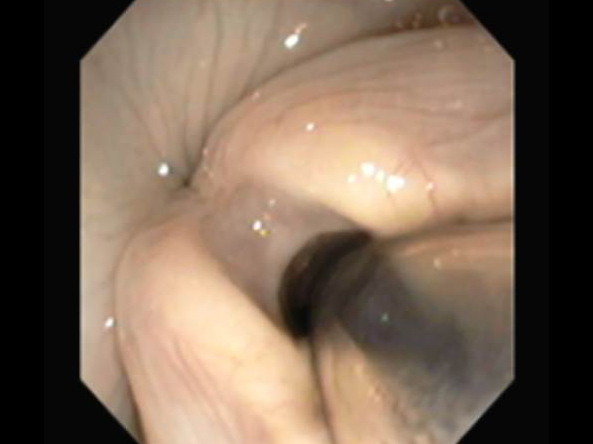

呼吸様式がおかしく鼻がつまった様な呼吸になったマルチーズの鼻腔内観察および生検を行ないました。

今回は麻酔下にて口から5.5mmの内視鏡を、鼻から2.8mmの内視鏡をいれ、咽頭部および鼻腔内の観察の両方を行いました。

左が咽頭部の写真です。粘膜面も綺麗で異常はありません。

右が鼻腔内の写真です。写真の左側に発赤、右側には粘液性の過剰分泌物が確認されました。

現在、適切な治療により状態は安定しております。